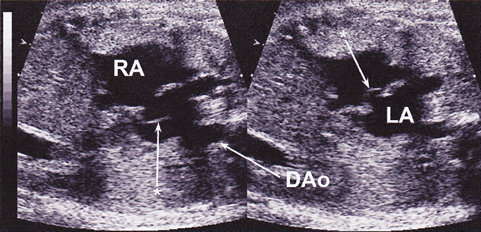

TGA,中でも生後緊急BASを要するようなTGAにおいては,その出生後の状態を評価して予測しておくことが重要である.1999年にMaenoらは,胎児TGA16例を検討し,胎児期のFO狭小とDA狭小が生後早期の予後に関連することを報告した26).具体的には16例中6例に胎児期FOの異常(fixed, flat, redundant)があって生後5例でFO狭小を認めた.また5例に胎児期DA狭小があり,生後は6例に狭小を認めた.DAが最も細かった4例中2例にFO異常もあり,その2例は出生直後に死亡,その他の1例は肺高血圧が継続した.2004年にJouannicらは,胎児TGA119例においてFOまたはDA狭小の評価を行い,24例でいずれかの異常を認めた(FO23, DA5,両方)4)が,13例で生後低酸素血症と代謝性アシドーシスをあり緊急BAS施行,FO狭小とDA狭小両方の2例は出生直後に死亡したと報告している39).しかし一方で胎児エコーによる予測は特異度84%,感度54%,FO狭小とDA狭小を合わせると特異度100%,感度31%と特異度は高いが感度は低いため他の指標も必要と結論している.2011年にPunnらは,TGAの新生児期緊急BASを胎児期に予測するものとして,新たに「hypermobile septum」(Fig. 7)と「reverse diastolic DA shunt」の二つが有用であると報告した40).具体的には,胎児TGA26例において卵円孔のhypermobility(一次孔を両心房間で揺れる),restriction, flat, redundancyを検証し,またDA径とシャントパターンも検証した.26例中14例で緊急BASを施行し,うち9例がhypermobileであり,8例で拡張期DA逆行を認めていた.Hypermobileと拡張期DA逆行は緊急BASと有意に相関があったとしている.いずれの報告も,胎児TGAにおいてはFOとDAの観察がその出生後の予後推定に重要であると結論付けている.